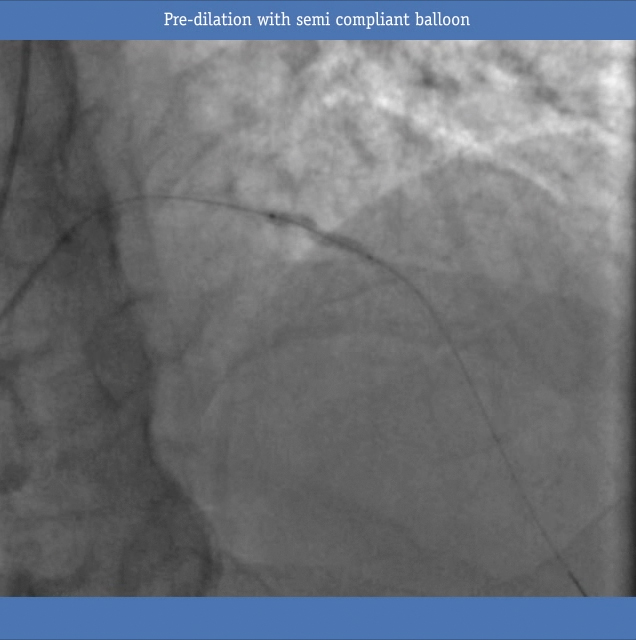

Pre Dilatation Reveals Calcium

• The COMET™ Pressure guide wire was disconnected and the lesion was pre dilated with a 2.5 x 20mm EMERGE semi compliant balloon.  Balloon inflation revealed significant calcium

• Due to significant calcium, the vessel was then treated with a non-compliant 2.5 x 15mm NC Quantum Apex. Next, the COMET™ pressure guidewire was re-connected and the resting Pd/Pa was 0.80. (not pictured)